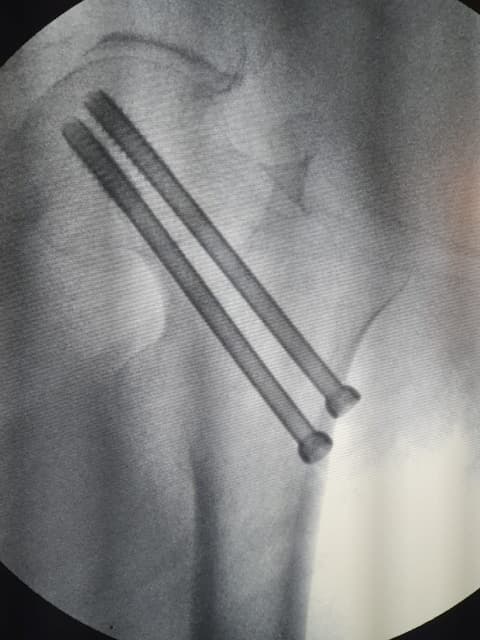

Internal Fixation-хагалгаа, дотор бэхэлгээ / тусгай хадаас

Хугарал засах мэс засал image4

DHS - Дунд чөмөгний гадна бэхэлгээ

Хугарал засах мэс засал image5

УНТЭ-т хийгдсэн мэс заслын зураг

Hip screw-Түнхний шураг

Хугарал засах мэс засал image6

Хугарал засах мэс засал image7